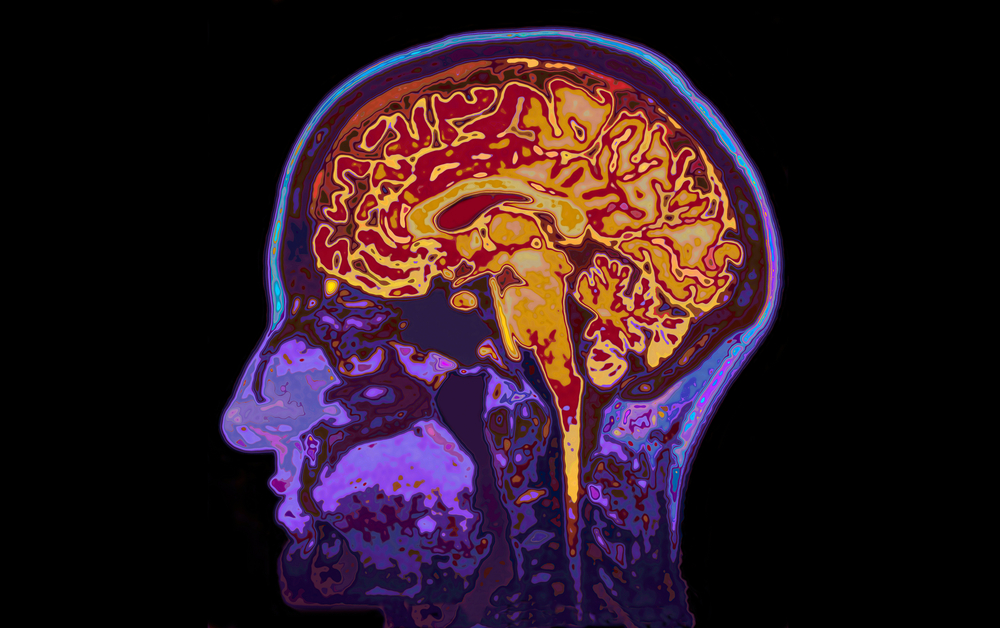

Покрај тоа, студијата покажува уште една голема корист на качувањето и симнувањето по скалите: Одржување на мозокот „млад“. Резултатите утврдуваат дека оваа активност ја зачувува сивата материја во мозокот со тоа што дава отпор на губењето или намалувањето на невроните, што го прави мозокот да изгледа и да функционира помладо.

Додека постепеното губење на сивата материја е неизбежно, тимот на Стефенер открил дека секое качување и симнување по скалите го прави мозокот помлад за 0,58 години. Податоците се откриле со скенирање на мозоците на повеќе од 300 доброволци на возраст од 19 до 79 години. Но, користењето на скалите не бил единствениот начин да се одржи младоста на мозокот. Според снимките, учењето имало голем ефект врз релативната старост на мозокот. Се открило дека со секоја година помината во учење, мозокот изгледал цела година помладо.